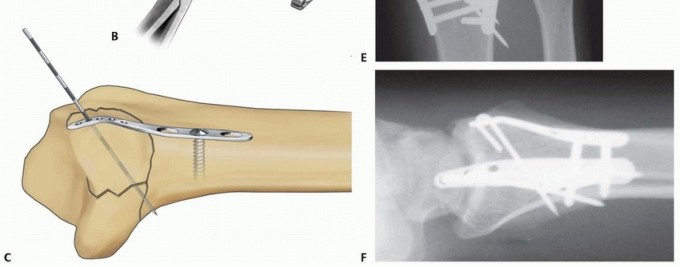

TECH FIG 8 • Radial column fixation with radial pin plate. A. Insertion of trans-styloid Kirschner wire. B,C. Creation of pin hook. D,E. Completion and impaction of pin hook. F,G. Completed radial column fixation. Select a distal pin hole and slide a radial pin plate over the trans-styloid Kirschner wire. Proximally, guide the plate under the tendons of the first dorsal compartment and secure it initially with a single 2.3-mm bone screw. Insert a second trans-styloid Kirschner wire through a nonadjacent distal pin hole. Use the previous technique to limit penetration of the Kirschner wire through the far cortex to 1 to 2 mm. Mark a reference point where the Kirschner wire crosses the surface of the plate. Withdraw the Kirschner wire 1 cm and cut it 1 cm or more above the reference mark ( TECH FIG 8B). Position the reference mark between the lower two posts of a wire bender and create a hook ( TECH FIG 8C). By starting the bend at the reference mark, this ensures that a Kirschner wire of proper length that extends 1 to 2 mm beyond the far cortex is created. Complete the bend with a pin clamp, overbending slightly to allow the hook to snap into an adjacent pin hole or over the edge of the plate ( TECH FIG 8D). With a free 0.045-inch Kirschner wire, predrill a hole to accept the end of the hook. Impact the Kirschner wire with a pin impactor and fully seat the hook ( TECH FIG 8E). Repeat the procedure with the second Kirschner wire. Complete proximal fixation with 2.3-mm cortical bone screws ( TECH FIG 8F,G). 2. ## Radial Column Fixation with Fixed-Angle Radial Column Plate 87 Expose and reduce the radial column with the technique described previously. Position the fixed-angle radial column plate and temporarily fix with a Kirschner wire both proximally and distally ( TECH FIG 9A). Confirm reduction of the radial column and plate position with the C-arm. Using fixed-angle drill guides, drill, measure, and insert locking fixation pegs of appropriate length into the distal fixed-angle holes in the plate and standard bone screws proximally into the shaft ( TECH FIG 9B-E).

TECH FIG 9 • Radial column fixation with fixed-angle radial column plate. A. Provisional placement of fixed-angle radial column plate. B. Drilling holes for distal fixed-angled pegs. C. Completed fixation. D. Unstable fracture injury films with segmental radial column comminution. E. Films 2 months postoperatively. Fixed-angle radial column support is used to avoid radial column shortening. 88 ## Ulnar Corner and Dorsal Wall Fixation Ulnar Pin Plate Through a dorsal approach, expose and reduce the dorsal ulnar corner fragment, dorsal wall fragment, or both. Insert a 0.045-inch Kirschner wire through the fragment ( TECH FIG 10A), angled proximally and slightly radially to purchase the far cortex of the proximal fragment. Insert structural bone graft into the metaphyseal defect if present to support the subarticular surface. If the plate is aligned along the pulnar border of the shaft, add a 15-degree torsional bend to the plate (twist the proximal end of the plate into slight supination). Often, a little extra extension can be contoured at the distal end of the plate ( TECH FIG 10B).

TECH FIG 10 • Ulnar corner fixation with an ulnar pin plate. A. Insertion of the interfragmentary Kirschner wire. B. Contouring the plate. C. Application of the plate and insertion of the initial fixation screw. D. Fixation completed. E,F. Radial and ulnar pin plate fixation of a three-part articular pattern (radial column and ulnar corner fragment). Slide the plate over the Kirschner wire and fix it proximally with a 2.3-mm bone screw ( TECH FIG 10C). Insert a second Kirschner wire if the fragment is large enough. Create and impact hooks as described for the radial pin plate ( TECH FIG 10D-F). If the Kirschner wire tips protrude beyond the volar cortex, they can be cut flush to the bone surface through a volar incision. Dorsal Buttress Pin Through a dorsal approach, expose and reduce the dorsal ulnar corner fragment, dorsal wall fragment, or both. Insert structural bone graft into the metaphyseal defect if present to support the subarticular surface. Insert two 0.045-inch Kirschner wires through the dorsal cortex and behind the subchondral bone; check the position with 89 the C-arm ( TECH FIG 11A). The Kirschner wires should be separated by about 1 cm and should be transverse to the longitudinal axis of the shaft; on the lateral view, it may be necessary to angle the Kirschner wires proximally to avoid penetration into the joint if the entry site is near the dorsal rim. Initially placing a dorsal buttress pin upside-down on the bone can be helpful as a template in order to visualize the proper position and insertion angle of the Kirschner wires ( TECH FIG 11B). Particular attention should be given to determining whether the insertion angle should include some pronation or supination in order to avoid torsion of the wire form as it is secured proximally.